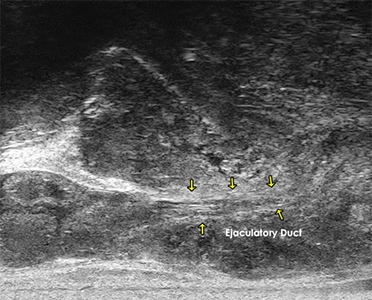

The 29 MHz ExactVuTM system facilities resolution down to 100 microns – and enables

detailed visualization in real-time of the prostate anatomy and characterization of

the prostatic tissue.

The following are select cases that are routinely derived from the ExactVuTM

micro-ultrasound platform and verified with pathological results.